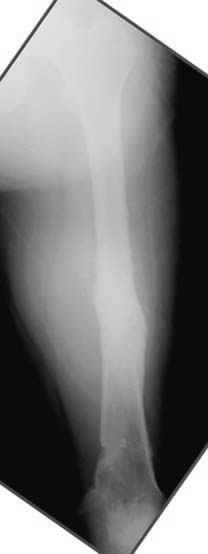

Несколько снимков из моей коллекции, чтобы разьяснить, почему мы до сих пор делаем различные варианты остеотомии.

На рисунке N1 предоперационный план лечения ложного сустава шейки бедра- линия ложного сустава, угол и направление введения импланта, клиновидная остеотомия в градусах и миллиметрах, второй снимок после коррекции, расчет, на сколько удлиняется конечность и размеры импланта;

N3 рисунок окончательный снимок, после операции моя рентгенограмма должен выглядеть примерно как эта картина. На N4 снимке клин перед удалением; N5 послеоперации 3 нед.; N6 окончательная рентгенограмма.

(доложен в Ст. Петербурге 2003 и в Москве 2004)

Отправитель: Djoldas Kuldjanov 23 Ноябрь 2004, 18:21

пластическая модель; и коррекция бедра аппаратом Илизарова.